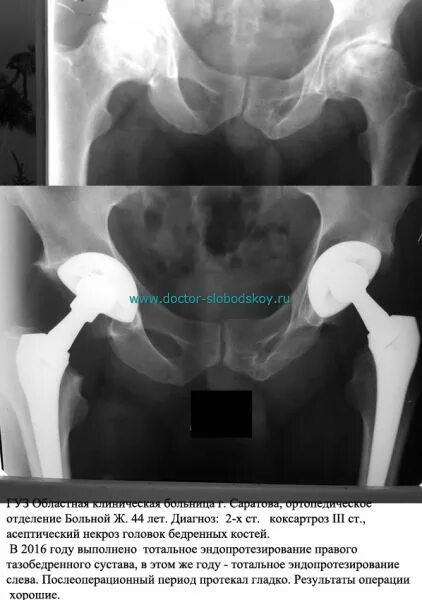

Некроз тазобедренного сустава лечение без операции